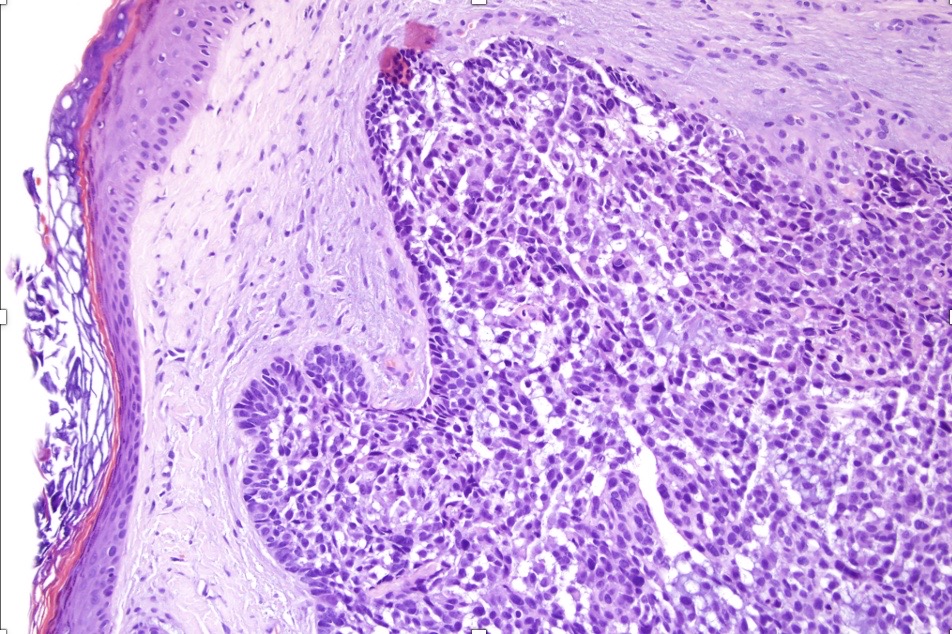

An exceedingly rare collision tumor composed of an admixture of squamous cell carcinoma/basal cell carcinoma/trichoblastoma respectively and melanoma. Although most appear to have behaved in a benign fashion, a malignant basomelanocytic tumor is illustrated below. More cases will be need to be stidies/published before the true biological behavior of this group of tumors can be satisfactorily elucidated. I think that complete excision should be the rule and a careful follow-up recomended.

Basomelanocytic tumor

Squamomelanocytic tumor